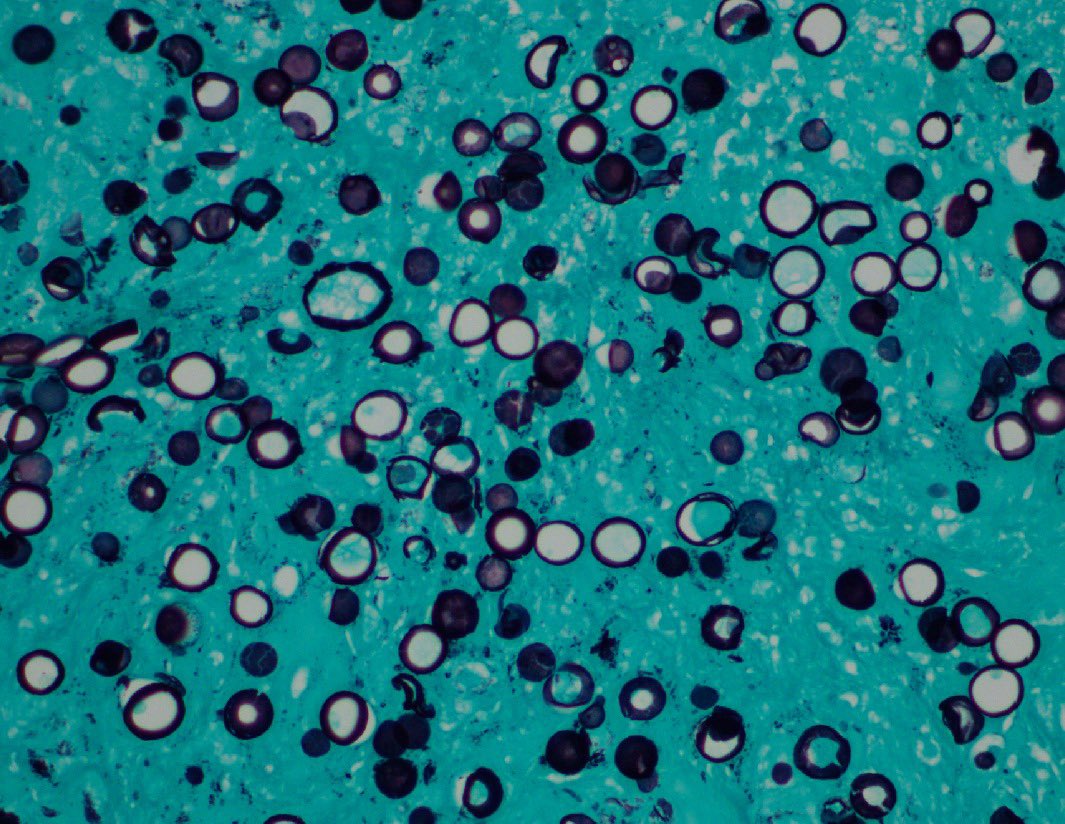

"BOW TIE". Papillary thyroid carcinoma. #FNA Thyroid. #Entpath #endopath #pathology #pathtwitter #PathTweetAward @MSWPathology @MyCytopathology @SamKhader